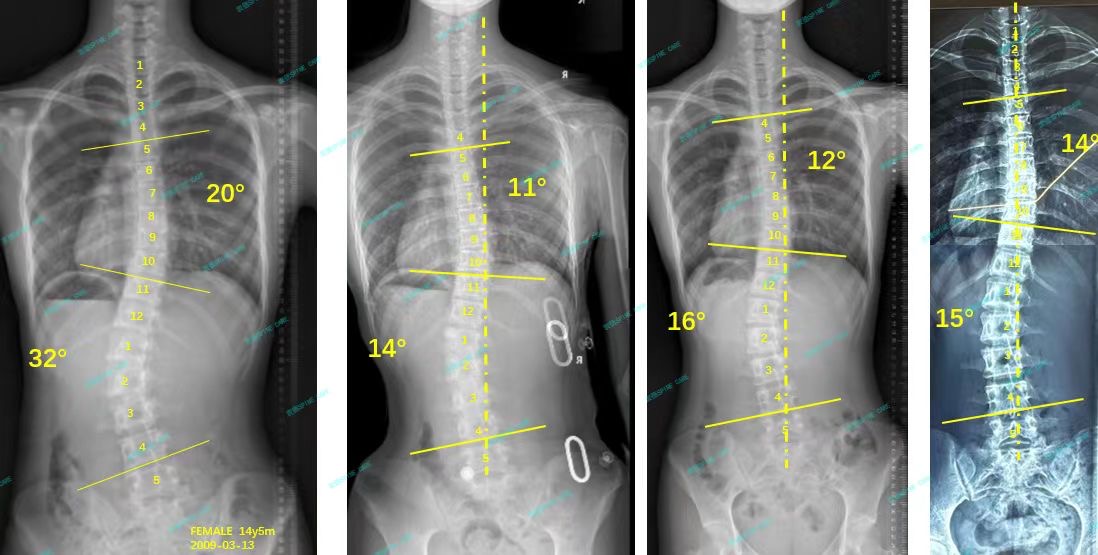

我是苗苗,从32度到15度,我又可以昂首挺胸了!

案例主人:苗苗 发现侧弯年龄:16岁 侧弯情况:Cobb角测32°

你好,我叫苗苗,胸弯20度,腰弯32度。妈妈很早就发现了我有脊柱侧弯,于是从网上找了一家私立机构带我每天去做训练,做了半年多,但是没有任何好转,于是来到了衷德脊柱。

Hello, my name is Miaomiao, with a chest bend of 20 degrees and a waist bend of 32 degrees. My mother discovered that I had scoliosis very early, so she found a private institution on the Internet to take me to do daily training. I did it for more than half a year, but there was no improvement, so I came to Zhongde Scoliosis Clinic and Research Center.

杨博士看了我的x片并且评估了我的体态之后,建议我做ZDT矫正训练+佩戴支具,我和妈妈在杨博士的专业下决定试试。一开始戴支具拍片的效果很好,我也每周都坚持来衷德脊柱做训练,每天也都坚持戴支具,后来脱支拍的x片显示我的度数已经降低了一半了!这样让我也更有动力继续坚持训练。

After Dr. Yang looked at my x-ray and evaluated my posture, he suggested that I do ZDT corrective training + wear brace. My mother and I decided to try it under Dr. Yang's major. At first, the results of taking x-ray with braces were very good. I also insisted on coming to Zhongde for spinal training every week and wearing braces every day. Later, the x-ray taken with braces showed that my degree had dropped by half! This also gives me more motivation to continue training.

来到衷德不知不觉两年多了,我和妈妈都十分信赖杨博士和所有康复师,最近脱支后拍x片显示我的胸弯从20度降到了14度,腰弯从32度降到了15度,我很开心!

It has been more than two years since I came to Zhongde without realizing it. My mother and I trust Dr. Yang and all rehabilitation therapists very much. Recently, an x-ray without wearing brace showed that my chest bend dropped from 20 degrees to 14 degrees, and my waist bend dropped from 32 degrees to 15 degrees, I am very happy!